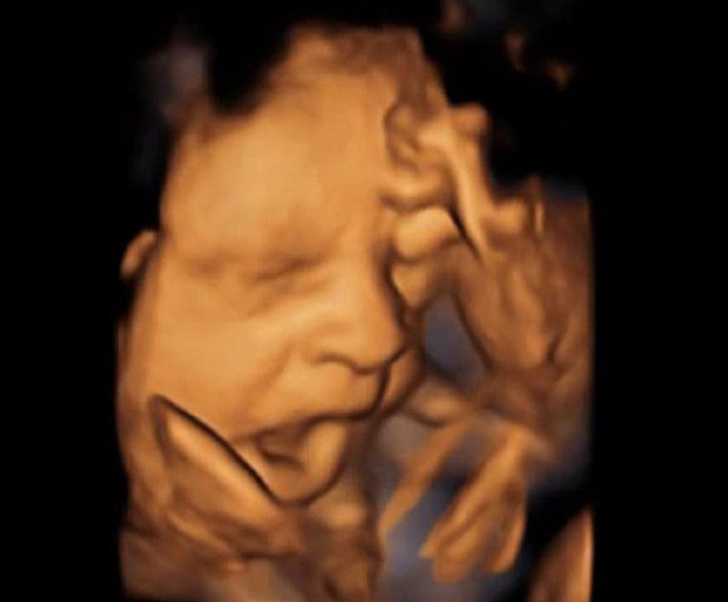

Дитина позіхає. 3D-УЗД на 36-му тижні вагітності.

В цей час дитина виглядає майже так само, як і тоді, коли з'явиться на світ. Він ще досить худенький, але шар підшкірного жиру збільшується все інтенсивніше. Однак і волосся, і нігті у нього вже повністю сформовані, а він сам стає настільки великим, що йому майже не залишається простору для маневрів, тому він може рухатися менше, ніж на більш ранніх стадіях.